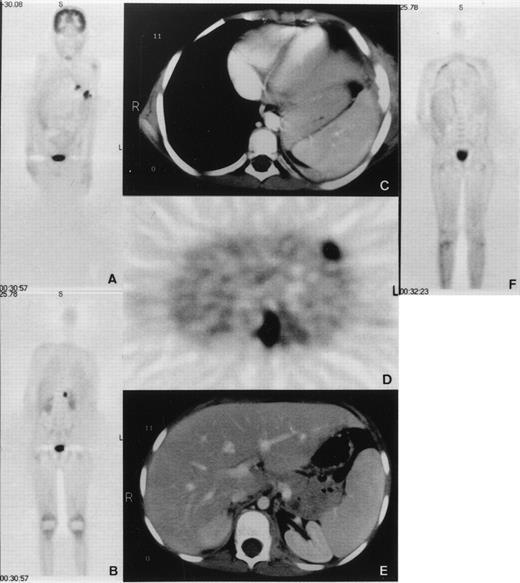

An 8-year-old boy with X-linked CGD (G828→A mutation in exon VIII resulting in a premature translation stop at amino acid position 272 and complete gp91-phox deficiency) was hospitalized because of pneumonitis. The patient had been under cotrimoxazole prophylaxis since the diagnosis at 8 months of age, and additionally under itraconazole prophylaxis since 3 years of age. No serious infections occurred until the age of 7 years when he developed a lingula pneumonitis after having stopped itraconazole for 4 weeks. After 5 months of unsuccessful treatment with various antibiotics, cultures taken from bronchoalveolar lavage showed growth of Aspergillus nidulans (A nidulans). The patient was treated for another 5 months with conventional amphotericin-B and γ-interferon, without improvement. Lingulectomy was performed with subsequent reisolation of A nidulans from excised lung tissue and pleural swabs. All isolates were susceptible to amphotericin-B and itraconazole, as determined by broth dilution method (MIC = 0.25 mg/L for conventional amphotericin, 0.25 mg/L for itraconazole, 1 to 2 mg/L for liposomal amphotericin B; AmBisome; Nexstar, San Dimas, CA). A second infectious agent, Actinomyces viscosus (A viscosus), was also repeatedly isolated from the previous bronchoalveolar lavage as well as from that performed during lingulectomy. These isolates were all susceptible to ciprofloxacin (MIC = 3 mg/L). The patient was administered liposomal amphotericin B (8 mg/kg/d) together with γ-interferon after surgery. He was treated with ciprofloxacin (20 mg/kg/d) since the first isolation of A viscosus. Two months after lingulectomy and while under this treatment, the patient developed persistent fever, tachydyspnoea, and severe lumbar pain. Whole-body positron emission tomography (PET) using F18-fluorodeoxyglucose (FDG) demonstrated five hypermetabolic foci (Fig 1). Four of these were pulmonary consolidations, one directly extending to the adjacent chest wall with osteolytic changes of the sixth rib leading to fistula formation into the skin. The fifth focus was a psoas abscess causing the excruciating pain and showed A nidulans on computed tomography (CT)-guided needle puncture. All PET lesions were seen in the corresponding CT images. There was no epidural extension as shown by CT and PET. These findings demonstrated that the conservative treatment had been unsuccessful. We elected to perform an emergency BMT from the HLA-genoidentical sister of the patient.

(A and B) Coronal emission FDG-PET scan before BMT. PET shows multiple inflammatory lesions in the lungs and an inflammatory focus in the upper left psoas with an intense FDG uptake. Physiologic high FDG uptake is seen in the brain, kidneys, and bladder. (C, D, and E) Axial transmission corrected FDG-PET image and corresponding CT images. Both PET and CT show inflammatory lesions in the left lung invading a rib and in the left psoas. (F) Coronal emission FDG-PET scan 3 months after BMT. Hypermetabolic lesions have disappeared.

The clinical course was surprisingly good with healing of the fistula over the rib and normalization of C reactive protein (CRP) on day 11 post-BMT (Fig 3). Cough disappeared after the third week. Fever persisted during the earlier weeks probably because of infection and afterwards, possibly due to GVHD. Starting on day 49, the patient developed grade III liver and grade I skin GVHD. In addition to cyclosporine-A, he was administered anti–interleukin-2 (IL-2) monoclonal antibodies (MoAb) (BB-10, BT 563, Leucotac; Biotest, Othmarsingen, Switzerland) at 0.4 mg/kg/d intravenously (IV).26 Steroids were excluded from the GVHD treatment because of their deleterious effects on PMN functions.27 28 The anti–IL-2 MoAb was administered daily until day 95 and every other day until day 109. Significant regression of the infiltration in CT and disappearance of the active inflammatory sites in PET were observed 3 months post-BMT (Fig 1). The cellular immune recovery was full at 4 months. Liposomal amphotericin-B was then replaced by oral itraconazole at 10 mg/kg/d. The patient was discharged at 5 months after BMT. At the time of preparation of this report, the patient, 2 years post-BMT, is doing well with no sign of infection or GVHD. He was substituted with IV immunoglobulins monthly until 12 months post-BMT. The karyotype analysis done on the mononuclear cells from peripheral blood showed 100% donor chimerism. The granulocyte function studies also demonstrate that they are of donor origin (Table1 and Fig 4).

The FDG-PET scanning, a sensitive imaging modality to evaluate tissue glucose utilization, was used to monitor the extent and the activity of aspergillus infection. Besides malignant tumors, inflammatory disorders show a high FDG uptake because of their increased glucose metabolism. In FDG-PET scanning 3 months post-BMT, a normal glucose metabolism was seen in all known lesions in accordance with the clinical course. This observation shows that invasive, multifocal aspergillosis should not generally be considered a contraindication for BMT, because even in CGD, as shown by our case, preexisting invasive multifocal aspergillus infection can be controlled during aplasia after BMT and until cellular immune reconstitution. Although the survival of CGD patients under conventional therapy has improved remarkably, up to early adulthood, quality of life is relatively poor despite life-long antimicrobial prophylaxis. We conclude that HLA-genoidentical BMT should be considered in patients with CGD not responding to conventional therapy before irreversible changes have occurred.